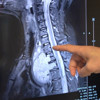

Prof. Dr. Güven Olgaç, “Hastamız bize başlıca nefes darlığı, yutma güçlüğü ve ciddi sırt ağrısı şikâyetleri ile başvurdu. Yaptığımız tetkikler sonucunda boyun bölgesinden başlayıp kalbine ve sırt omurlarına kadar uzanan, aynı zamanda nefes borusu ile yemek borusuna ciddi baskı oluşturan 12 santimlik bir kitle tespit ettik. Aldığımız biyopsi bize bu tümörün ‘iyi huylu’ olduğunu gösterdi ve hayati organlarda oluşturduğu ciddi baskı semptomları nedeniyle en iyi tedavi şeklinin cerrahi yöntem olduğunu bildiğimiz için ameliyat önerdik. Prof. Dr. Keramettin Aydın’ın önderliğinde Beyin Cerrahisi ekibimizin de katkıları ile beraber bu operasyonu gerçekleştirdik. Biz kitleyi şah damarı, kalp, akciğer, soluk borusu ve yemek borusundan ayırdıktan sonra beyin cerrahisi ekibimiz, kitlenin omurga ile olan yapışıklığını giderecek şekilde bir ameliyat gerçekleştirdi. Çok şükür, ameliyatı gayet başarılı oldu ve 10 gün içerisinde hastamızı taburcu ettik. Gülsüm şimdi ameliyat sonrası 3. ayında ve artık normal hayatına döndü diyebiliriz. Yaptığımız kontrollerde tümörün tamamen alınmış olduğunu ve önceden tümör basısına maruz kalan tüm hayati organların normale döndüğünü gördük” şeklinde konuştu.

“OMURGAYA UZANAN BÖLGEDE PORTAKAL BÜYÜKLÜĞÜNDEKİ TÜMÖRÜN TAMAMINI ÇIKARDIK”

Beyin ve Sinir Cerrahisi Kliniği’nden Prof. Dr. Keramettin Aydın ise “Göğüs cerrahisi kliniği ile birlikte yaptığımız incelemelerde, kalbin arkasında omurgaya uzanan bölgede yaklaşık bir portakal büyüklüğünde kitle olduğunu gördük. Dünya Tıp literatüründe son derece nadir rastladığımız bu ameliyatı Göğüs Cerrahisi ekibimiz ile birlikte planladık. Ameliyat sırasında önce göğüs ön duvarını açtık ve daha sonra sırt bölgesinden 'torakotomi' dediğimiz ek bir yaklaşımla tümörün omurga ile ilişkisini ortaya koyduk. Öngördüğümüz gibi tümörün sinir kaynaklı olduğunu tespit ettik ve ilişkili omurgaların sadece bir kısmını temizleyerek tümörün tamamını çıkarmamız mümkün oldu. Böylece hastamızın omurgasına, daha sonraki yaşamında sırt hareketlerini kısıtlayacak bir platin desteği koymak zorunda kalmadık. Multi-disipliner ‘çok-disiplinli’ yaklaşımla gerçekleştirdiğimiz bu ameliyat, bu yönüyle de bizim için çok tatmin edici oldu ve hastamız şu anda, aktif günlük yaşamını olumsuz etkileyen herhangi bir hareket kısıtlılığı olmaksızın normal şekilde yaşantısını sürdürebiliyor”